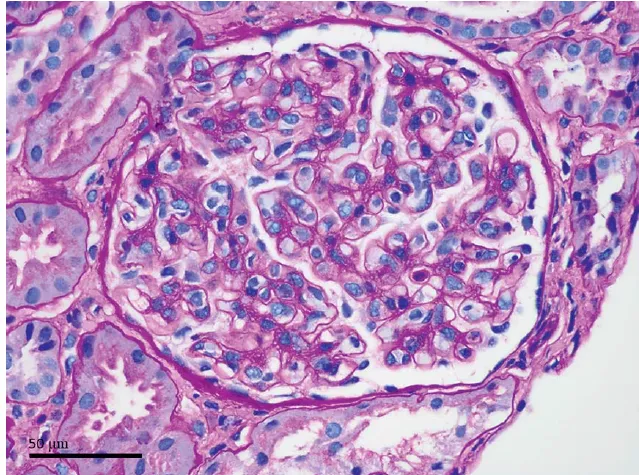

Achados laboratoriais mostraram apenas anemia microcítica e hipocrômica leve. O exame de urina evidenciou

leucocitúria, nitritos negativos, ausência de proteinúria e hemácias sem dismorfismo eritrocitário. O exame de urocultura foi negativo.